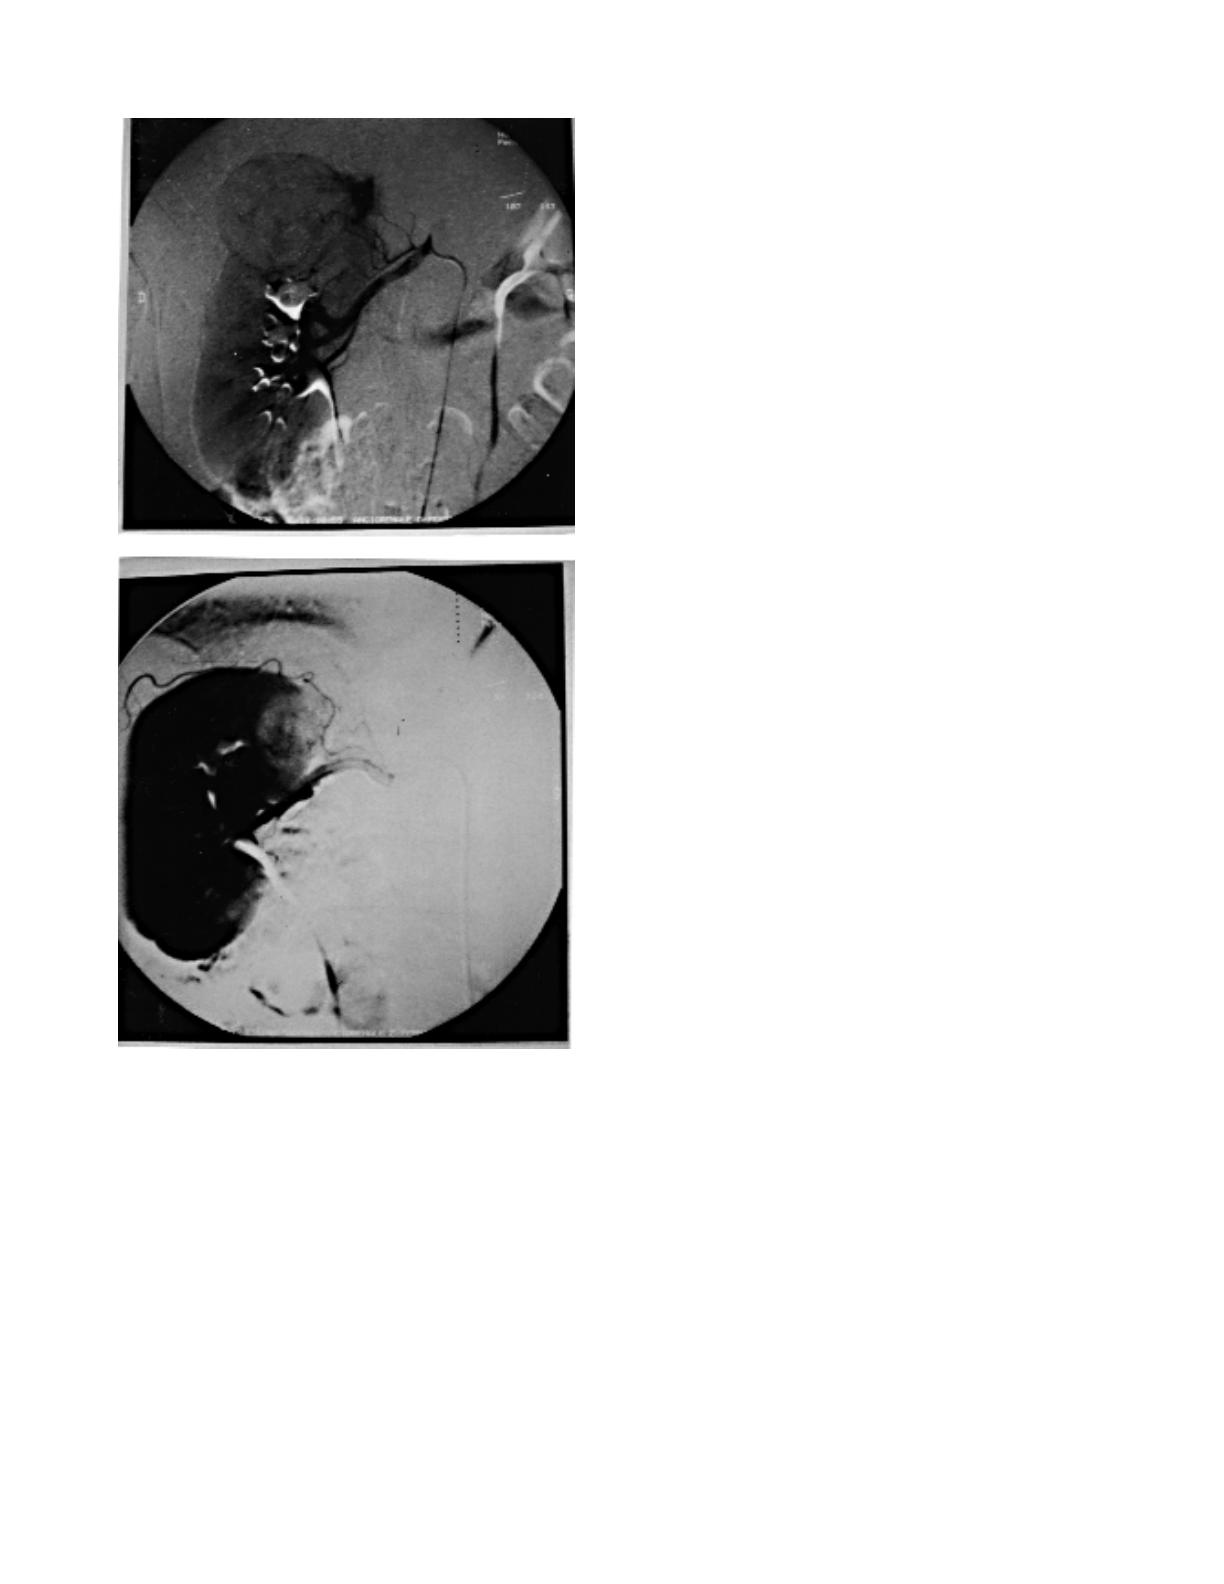

est homogène. L'artériographie montre une

tumeur hypervascularisée dans 3 cas, tous des

cancers, et hypovascularisée dans 7 cas : 2 can-

cers, 2 adénomes, 2 angiomyolipomes de très

petits volumes et un kyste hémorragique.